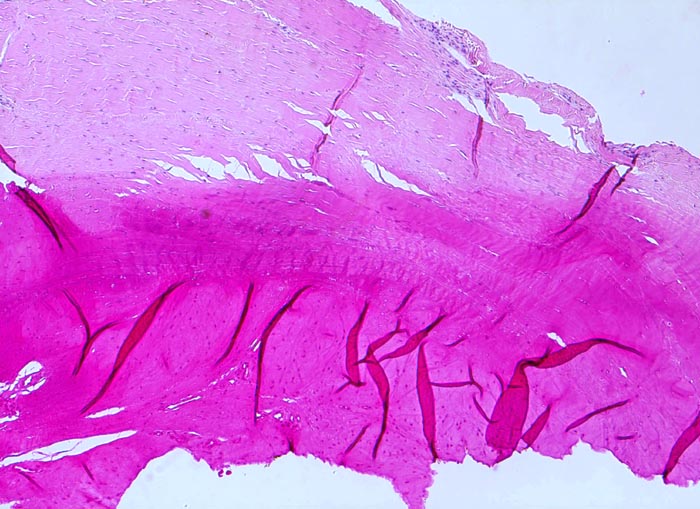

In Abhängigkeit von der Entzündungsdauer werden unterschiedliche morphologische Befunde beschrieben. Die initiale proliferative Phase ist charakterisiert durch eine Hyperplasie der Synovialis, Fibrinexsudate und Gelenkergüsse. In der destruktiven Phase kommt es zur Zerstörung von Gelenkknorpel und gelenknahem Knochen durch Ausbildung eines intraartikulären Pannusgewebes (> 194). Die ausgebrannte Phase ist gekennzeichnet durch eine synoviale Fibrose mit zunehmender Ankylose (= Gelenkversteifung).

Typische histologische Veränderungen sind eine synoviale Zottenhyperplasie, Verbreiterung der Deckzellschicht unter Einschluss mehrkerniger Riesenzellen, Fibrinexsudate und synoviale Ulzerationen, Infiltrate von Lymphozyten teils in Form von Lymphfollikeln, Plasmazellen, neutrophilen Granulozyten, Makrophagen und Siderophagen, sowie Einschlüsse von Knorpel- und Knochenfragmenten (Detritussynovialitis). Die histologischen Befunde der Synovialis korrelieren oft nicht mit den klinischen Angaben. Trotz fortgeschrittener Gelenkdestruktion mit ausgeprägter klinischer Symptomatik können Synovialektomiepräparate nur sehr geringe pathologische Veränderungen zeigen. Oft ist auch nicht mehr zu eruieren, welche Läsionen Folge der Grundkrankheit und welche Folge diverser intraartikulärer Therapien oder begleitender Superinfektionen sind.

Morphologische Merkmale:

• Synovialis mit verplumpten Zotten.

• Stark proliferierte mehrreihige synoviale Deckzellschicht.

• Herdförmig Fibrinauflagerungen durchsetzt von neutrophilen Granulozyten.

• Hyperzelluläres Stroma mit lymphoplasmazellulärem Entzündungsinfiltrat mit Ausbildung von Lymphfollikeln.